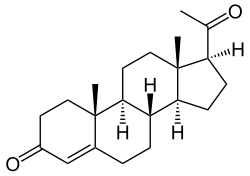

Como otros esteroides, la estructura de la progesterona consiste en cuatro hidrocarburos cíclicos interconectados, con grupos funcionales de cetona y oxigenados, como también dos sustituyentes metilo.